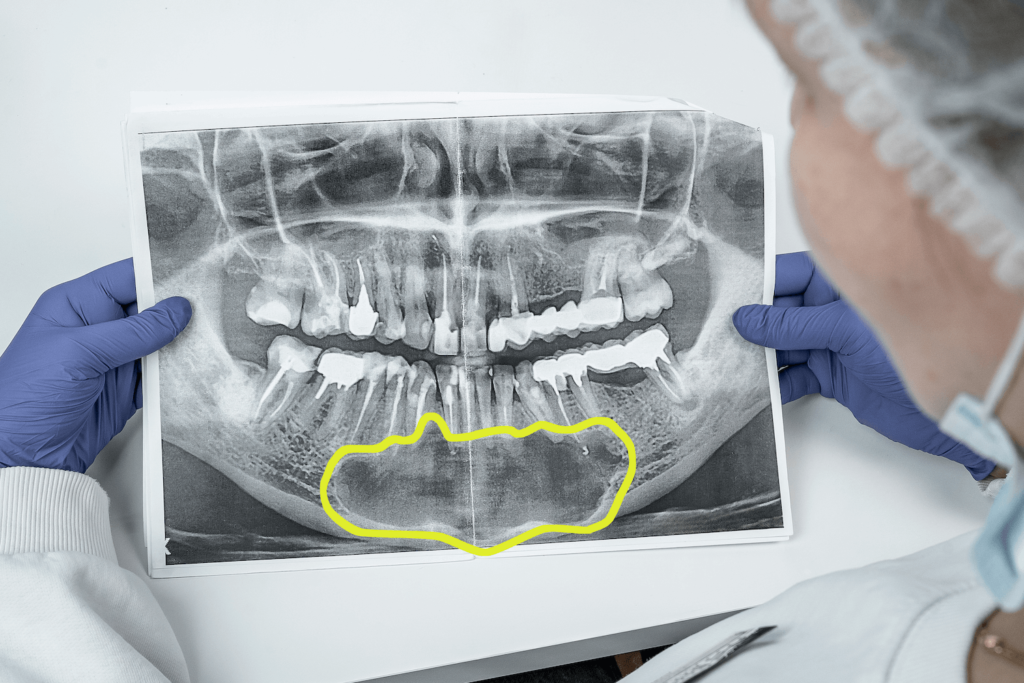

Около десяти лет назад к нашему врачу Максиму Макаренко обратилась пациентка с целью получить альтернативное мнение врача. Во время диагностики на панорамном снимке врач обнаружил интактные (здоровые) зубы на нижней челюсти и в области подбородка, в области апексов фронтальных зубов кисту с четким очертанием. Киста была достаточно большого размера, а именно от зуба 4.5 до зуба 3.5. То есть почти все зубы нижней челюсти были поражены новообразованием.

Дополнительно пациентку беспокоило онемение губы с обеих сторон, низа подбородка (из-за давления кисты на выход нерва из ментального отверстия).

Ранее пациентка посетила хирурга назначившего операцию по удалению новообразования — пациентка не соглашалась на операцию. Нежелание делать операцию было связано с тем, что существовал высокий риск потери зубов в результате образования полости после такой процедуры.